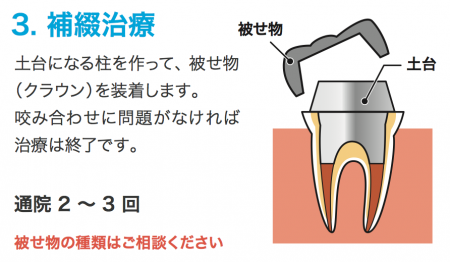

根管充填が問題なければ歯を補強する土台を作り、

被せ物をオーダーメイドで作ります

保険治療では銀歯になりますが

見た目が気になるようなら

白い歯を入れることも可能です